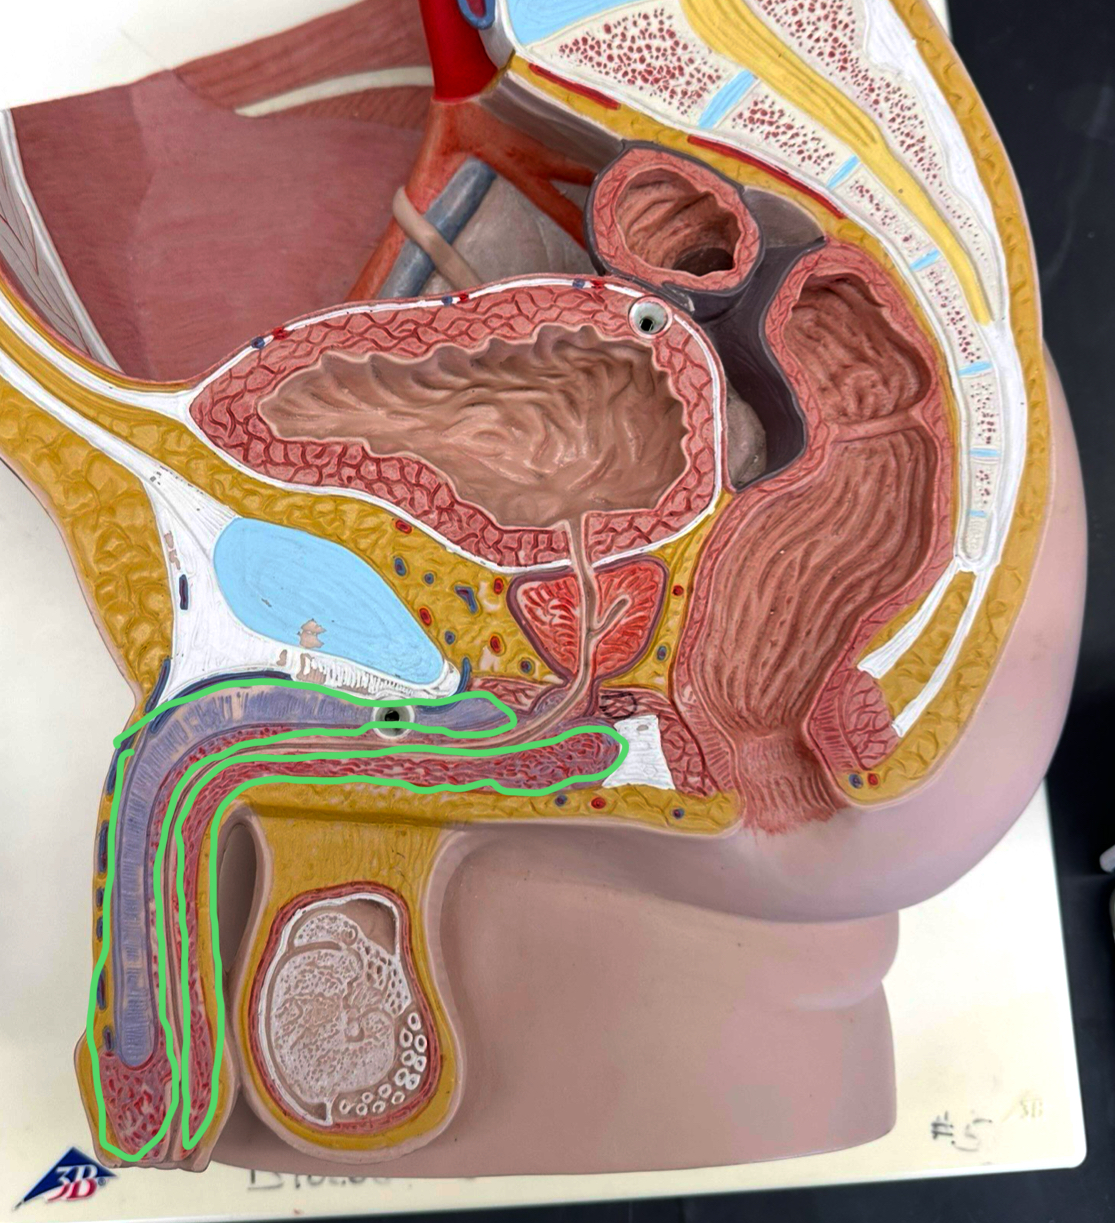

spermatic cord

ductus deferens

as a whole

erectile tissue

corpus cavernosum

corpus spongiosum